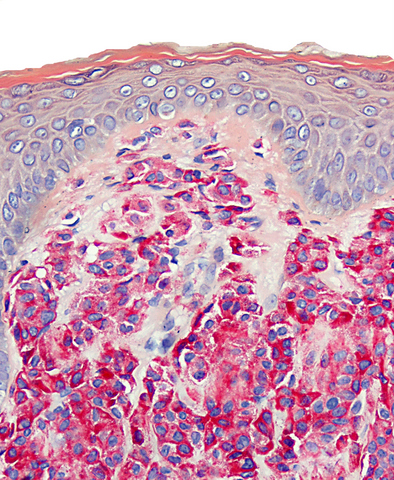

Microscopic (histologic) images

Positive stains

- Toluidine blue and Giemsa demonstrate metachromasia (granules are purple red)

- Leder (chloroacetate esterase), CD117 / c-kit